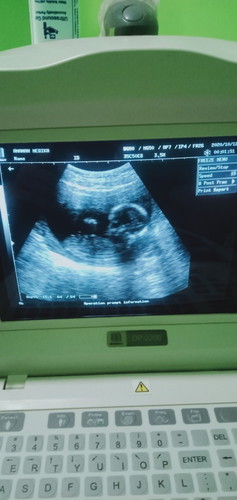

Seputar kehamilan

Kenapa yea Bun klo makan yang manis2 janin gerak nya lebih aktif๐๐

manis mengandung glukosa yg di ubah menjadi tenaga janin pun akan merasakanya jika kita konsumsi manis dia makin aktif